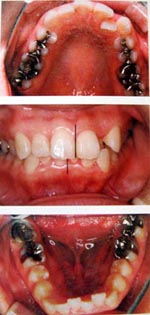

顎(あご)が小さいと、歯がきれいに並びきらないために、歯並びが悪くなりがちです。歯並びが悪いと虫歯や歯周病になりやすくなるだけではなく、いびきや無呼吸症候群になることがあります。

顎を成長させて、口の中の空間を広くし、歯並びも整えます。同時に空間が広がることにより、呼吸がしやすくなり、いびきや睡眠時無呼吸症候群を抑制することができます。

顎矯正(拡大矯正)SH療法は、1日10時間装置をはめて、あごを成長させる矯正です。お子様も大人も矯正することができます。

上記のような例で、症状が出ている場合、抜歯をせず口の中の空間を広くする装置を使用することで、症状をなくすことができます。

成人の場合・1日10時間装着

顎が小さく症状がある方には有効です。